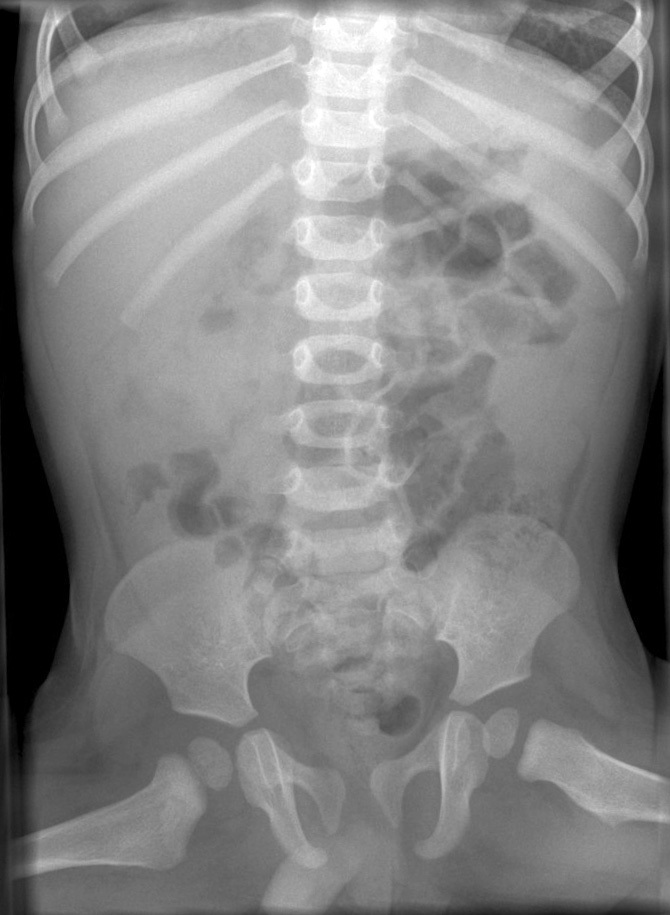

What is seen on this abdominal x-ray showing intussusception? Why is AXR indicated?

Essential to look for free air if the patient has signs of peritonitis and may have perforated.